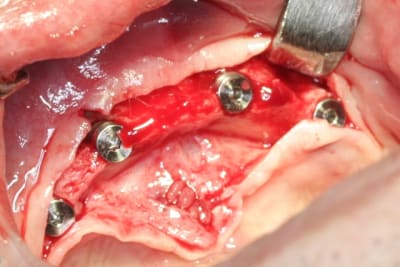

barre pour stabilisation du complet bas...;-)

le patient, niveau budget pouvait se permettre mieux...on aurait pu faire sans problème un all on six (ou plus) transvissé...si son état de santé avait été meilleur...pas très grave...mais son Parkinson lui complique l'hygiène buccale...alors passer des brossettes loin au fond...là au moins son épouse pourra l'aider...çà sera pas trop compliqué...et au niveau confort, c'est quand même pas mal...

mais le ptit plus de cette intervention...c'est pas les mêmes implants que d'hab...c'est des drive implant...pas mal du tout...du moins pour la chir...

forets super...avec butées clipsables (très pratique et sécurisant), super stab primaire...très sympa...

ah, celle là, je l'attendais...c'est court parce qu'il y a, après étude du scan...un gros, très gros canal incisif qui passe juste dessous...et qui donne un foramen mentonnier dans la zone antérieur...bien identifié...du genre à contenir un faisceau sensitif pour le menton et la partie médiane de la lèvre...tu vois ce que je veux dire...???

pour ce cas, j'ai posé en 34 et 44 des 4x8...et pour 32 et 42 des 4x10...

pour répondre à une autre de tes questions..."pourquoi pas les expanseurs"...simple...la bourde...l'assistante qui oublie de les mettre à stériliser...mais bon y manque pas grand chose en vestibulaire...et c'est aussi pourquoi j'ai mis des 4mm en 34 et 44...à l'origine je voulais mettre des 5mm...